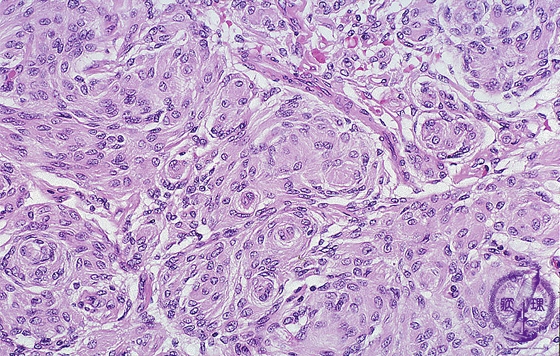

Microscopic findings (H.E. high magnification): Meningothelial meningioma showed a proliferation of tumor cells with round nuclei and unclear cellular junctions. Whorl formation of the tumor cells was seen in a scattered pattern within the tumor nests.